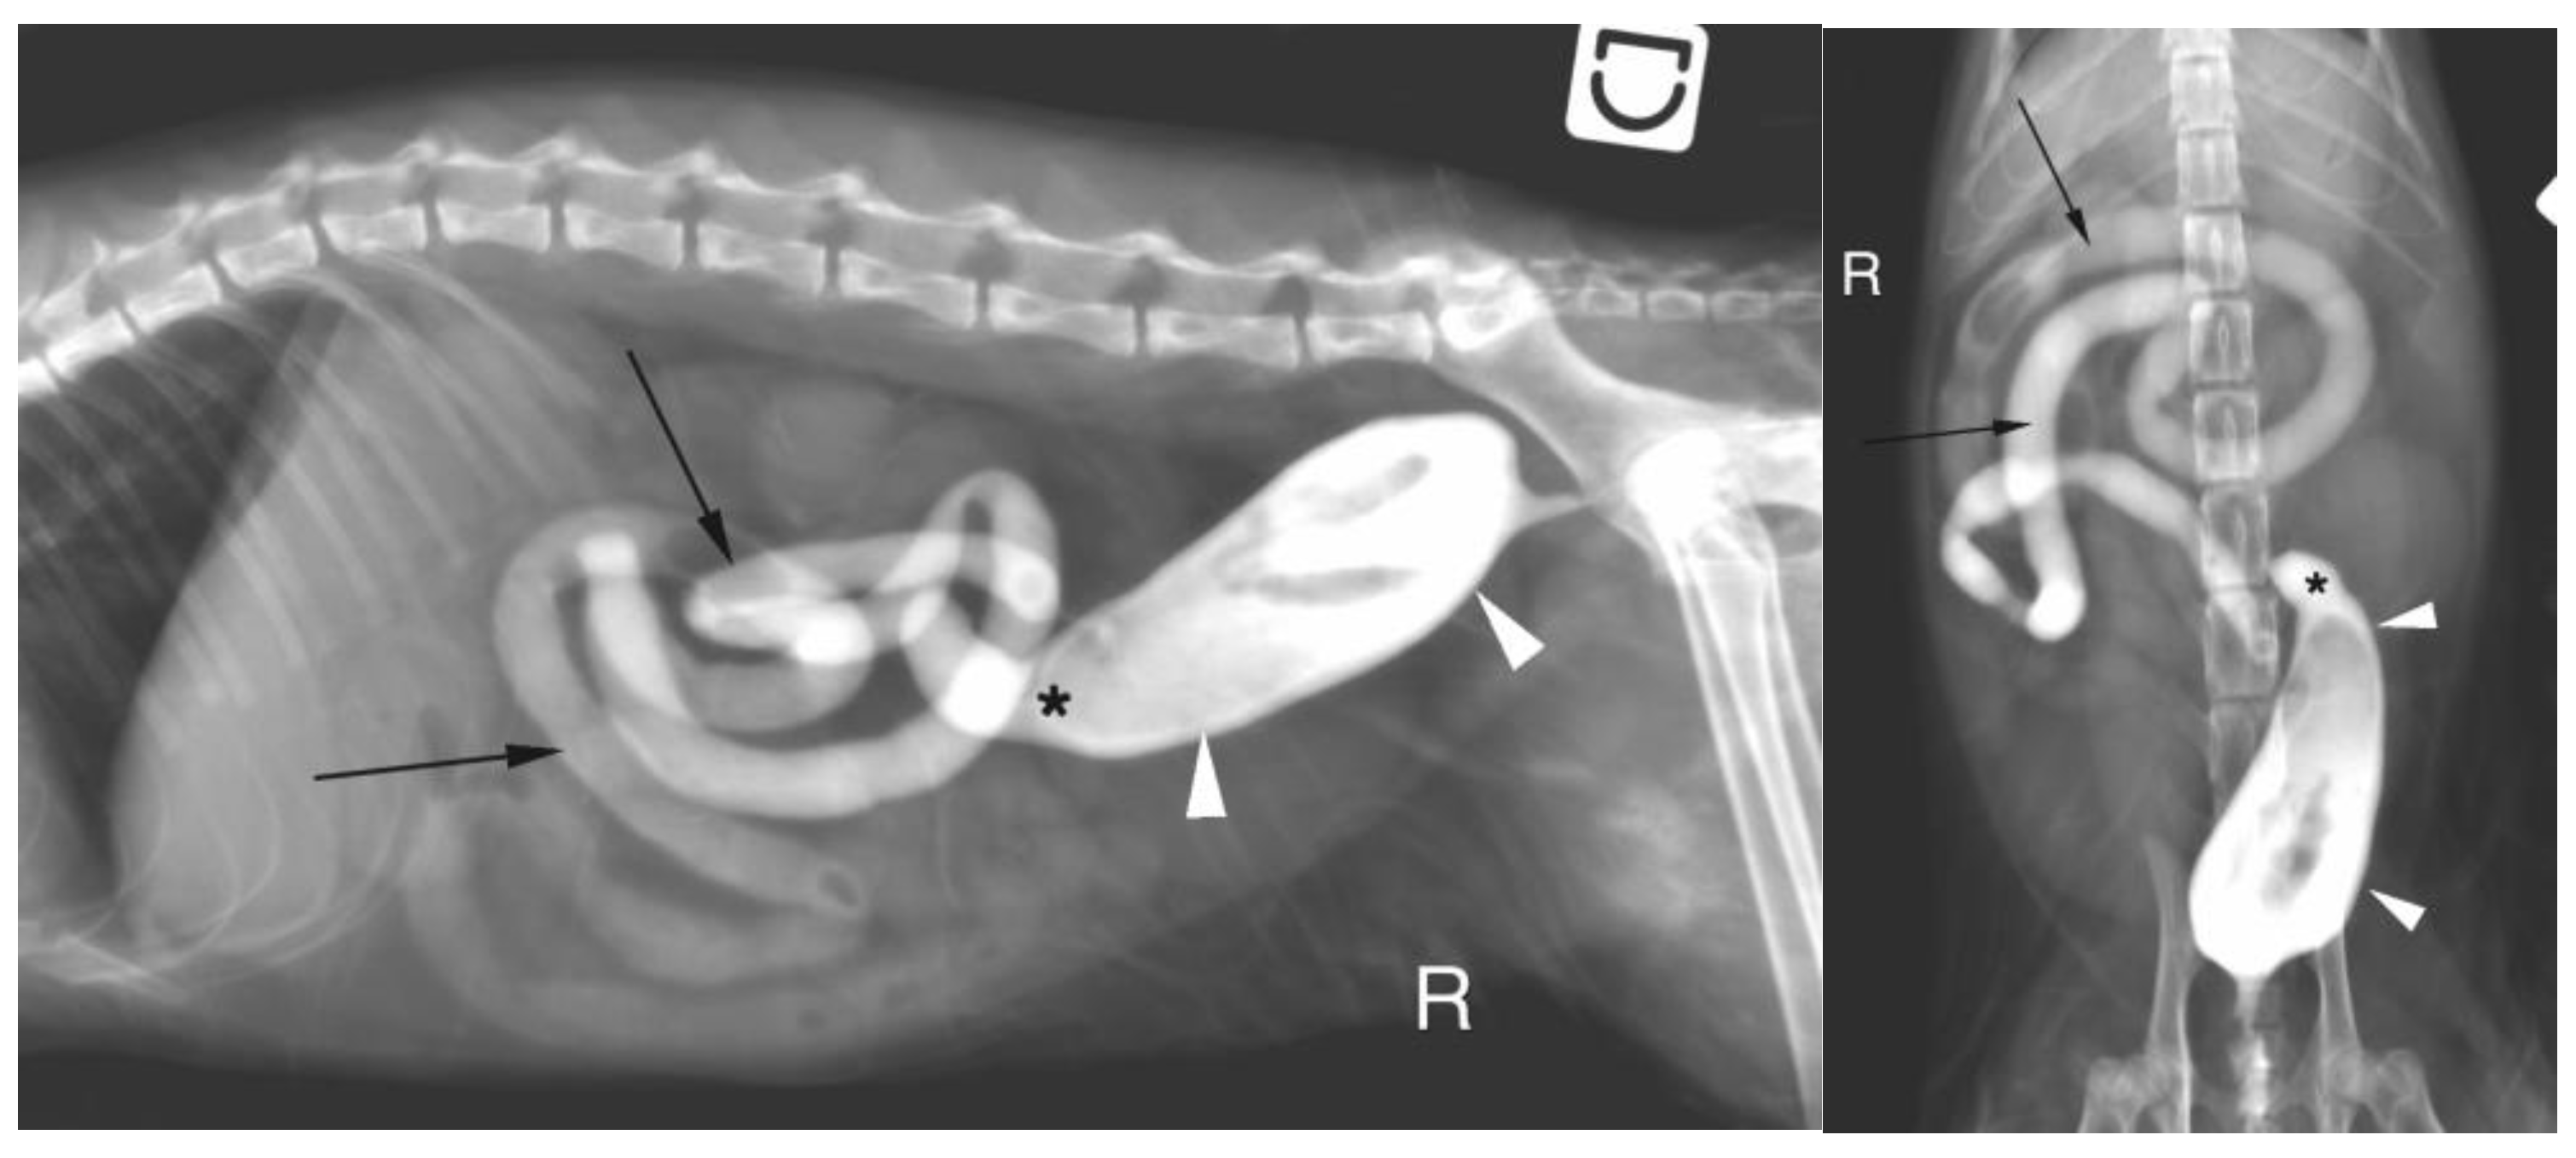

Abdominal radiographs were acquired in 5 cases (4 cats and one dog). In two cats, the descending colon showed an abrupt ending with a total length approximately half as long as expected. No ascending nor transverse colon could be identified in these 2 cases (Figure 2). In the dog, the cecum appeared mispositioned in the left cranial abdominal quadrant and seemed associated with a focal area of colonic lumen narrowing 22 cm orally to the anus (Figure 3). Positive contrast colonography were performed in 3 cases (three cats) and allowed the diagnosis of partial colonic agenesis in all of them (Figure 4).

Figure 4. A. Right lateral radiograph and B. Ventro-dorsal radiograph of the abdomen of the same cat as on image 2, during positive retrograde colonography. The descending colon is shorter than expected (white arrow heads), the ileocolic junction is identified as a narrowing of the colonic lumen orally (asterisk). Contrast medium is also visible within the small intestine (black arrows). The cecum is not identified.